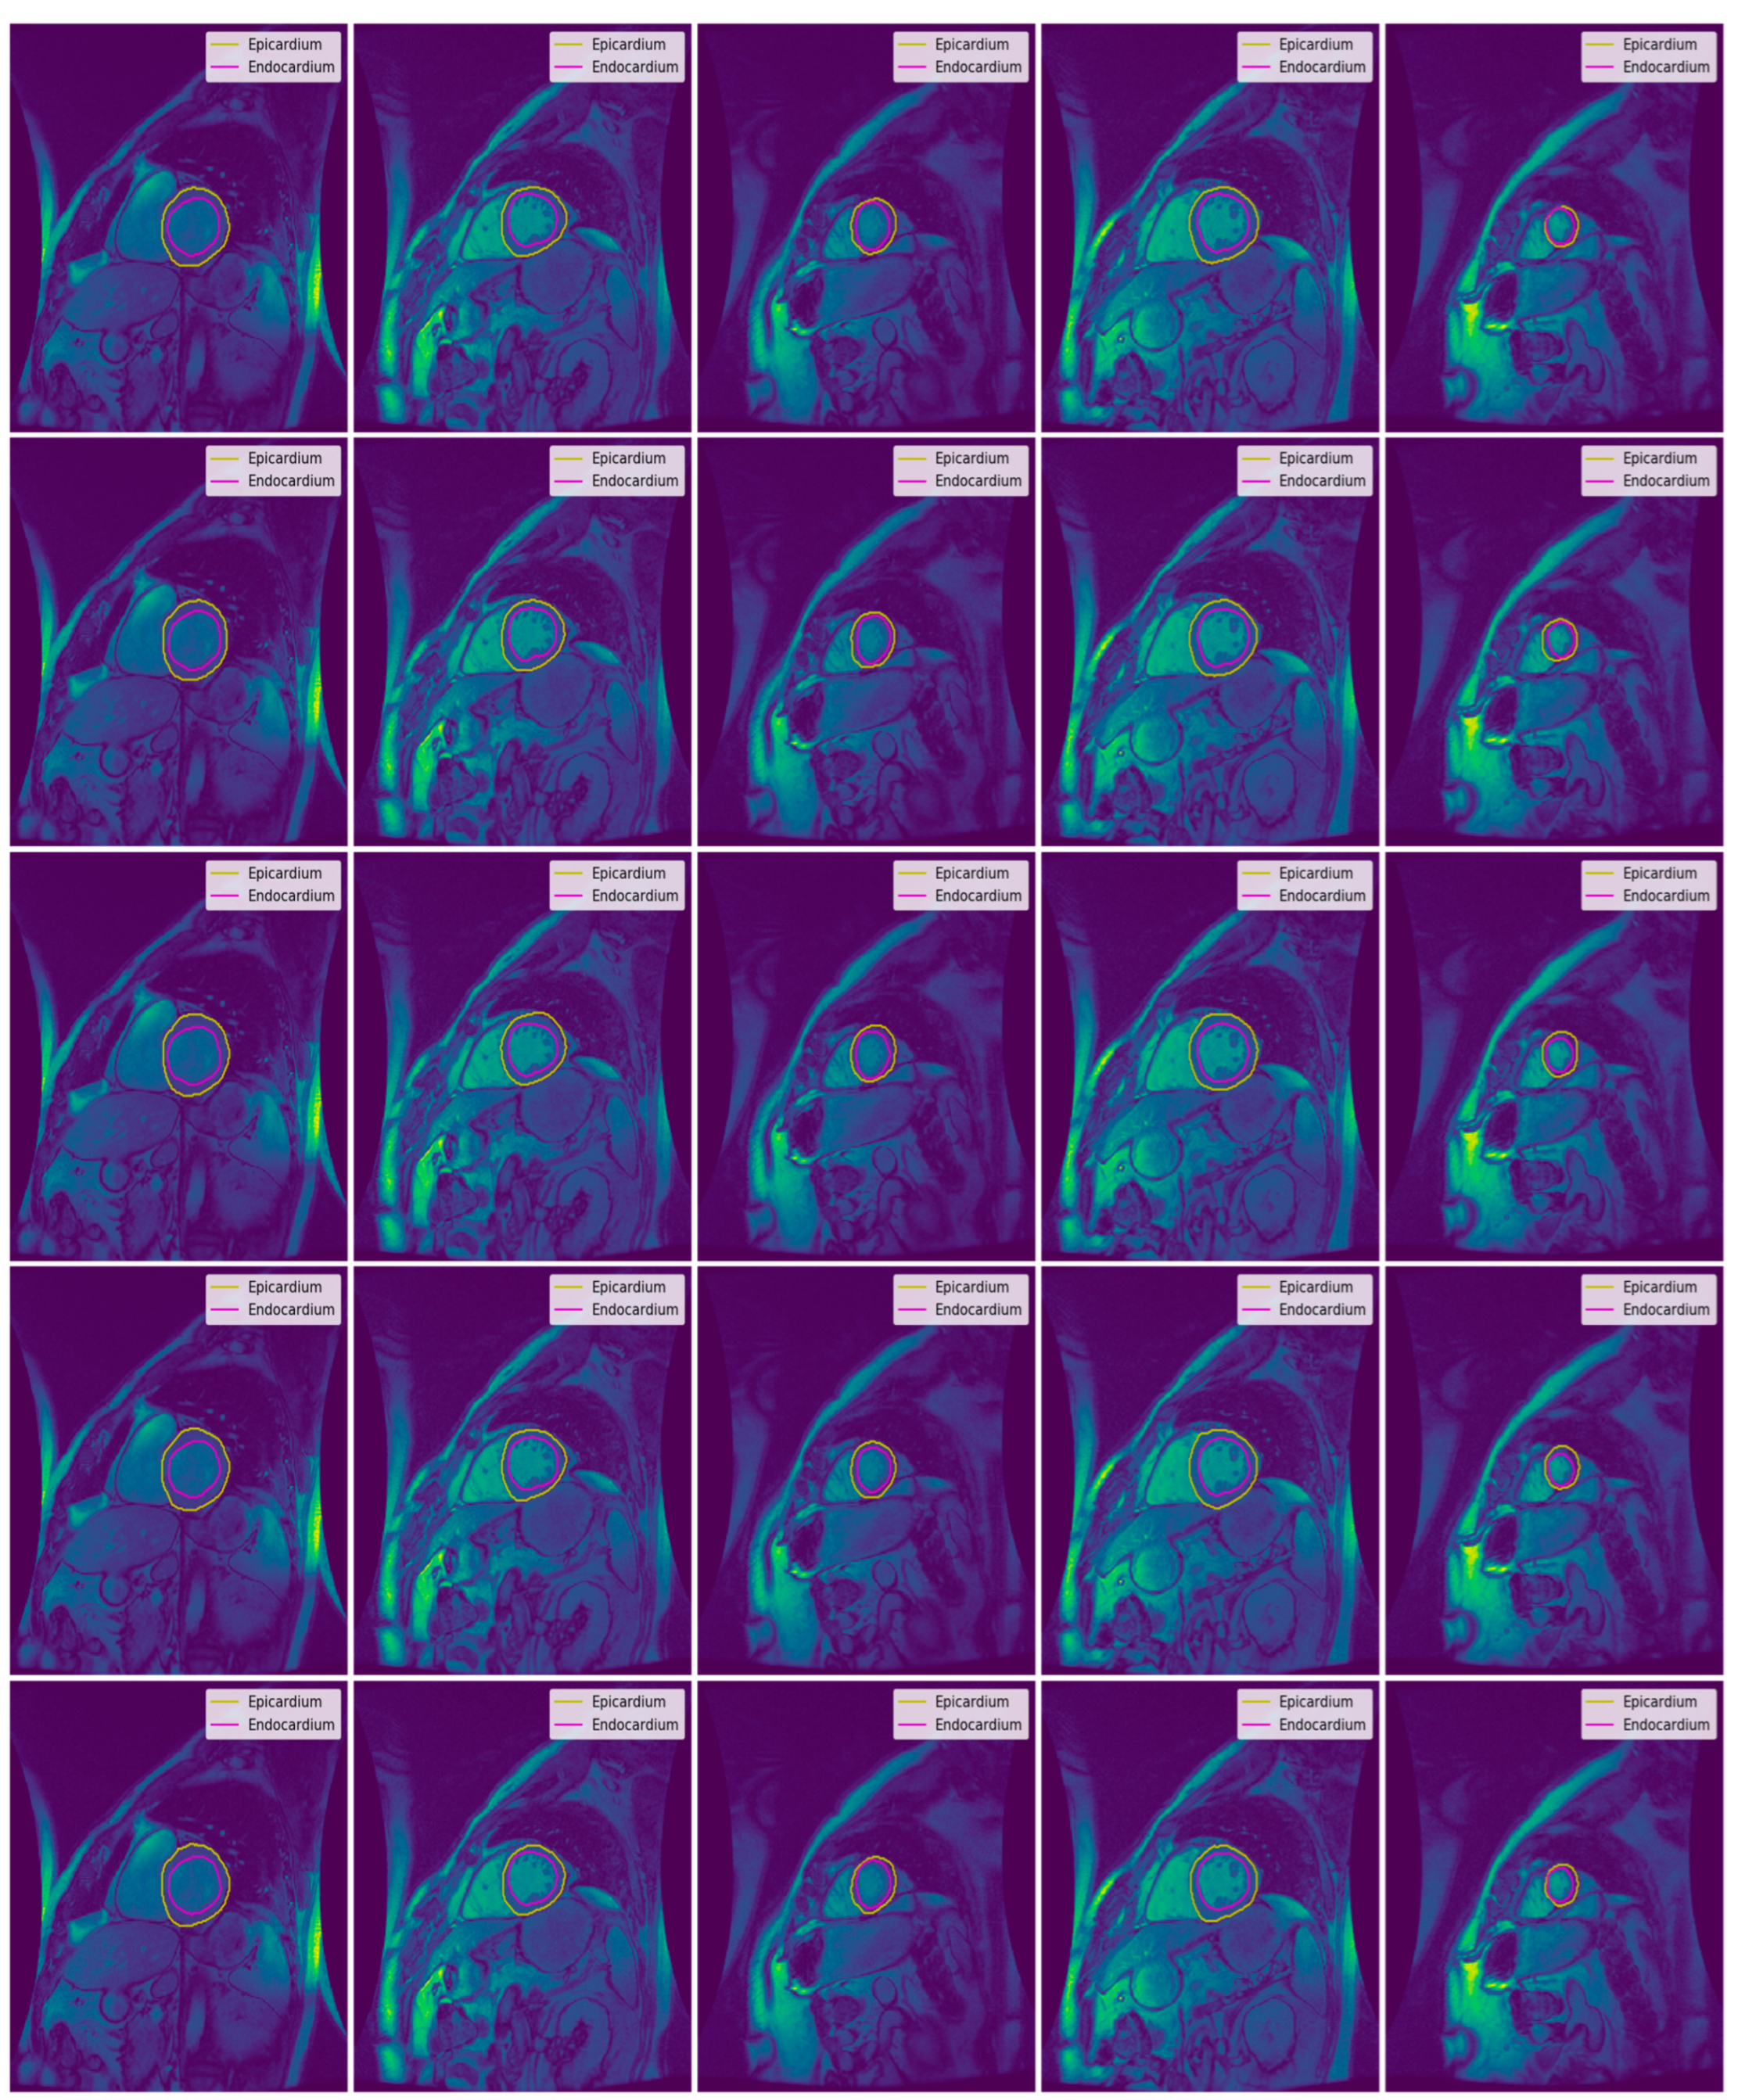

3.3. Illustrated Results

- U-Net with focal Tversky loss;

- U-Net with log-cosh dice loss;

- U-Net with Tversky loss;

- U-Net with dice loss; and

- U-Net with binary cross-entropy loss.